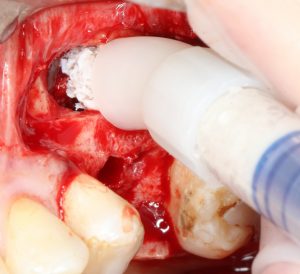

Пришло время вернуться к синуслифтингу и заполнить сформированное ранее субантральное пространство графтом (Geistlich Bio-Oss Pen):

запечатываем заполненное субантральное пространство:

Как это правильно сделать, читайте здесь>>, здесь>> и здесь>>.